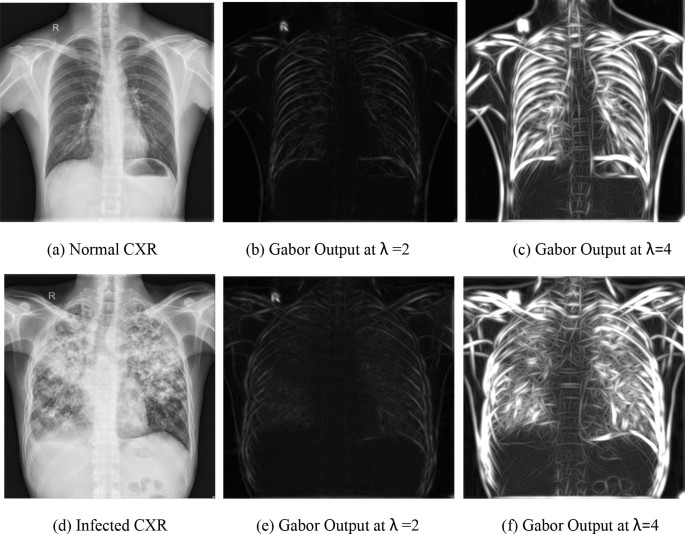

where mx and my represents the center of respective field in image coordinates and σx, σy represent the standard deviation of respective field. λ represents the wavelength of sinusoid. γ represents the orientation and Ψ represents the phase offset. For certain abnormalities like infiltrates, TB infected CXR images contain more frequency elements than a normal CXR image. So, Gabor filter was applied to the input image with two different values of wavelength (λ), i.e. λ = 2 and λ = 4 with orientation varying from 0 to 360.

For Gabor filter, input image was down-sampled to 300 × 300 pixels. The result is two different images showing the presence of certain frequency elements in the input image. For each input CXR image, there are different levels of abnormalities. In certain images, the abnormalities are clear enough to be detected at low value of wavelength while for some other images, larger value of wavelength works better. Figure 2 shows Gabor filter output for normal and infected input CXR images. Figure 2b, e shows Gabor filter output image at λ = 2 while Fig. 2c, f shows Gabor filter output image at λ = 4.

Gabor filter ouput on sample CXR images. (a) Normal CXR, (b) Gabor output at λ = 2, (c) Gabor output at λ = 4, (d) infected CXR, (e) Gabor output at λ = 2, (f) Gabor output at λ = 4